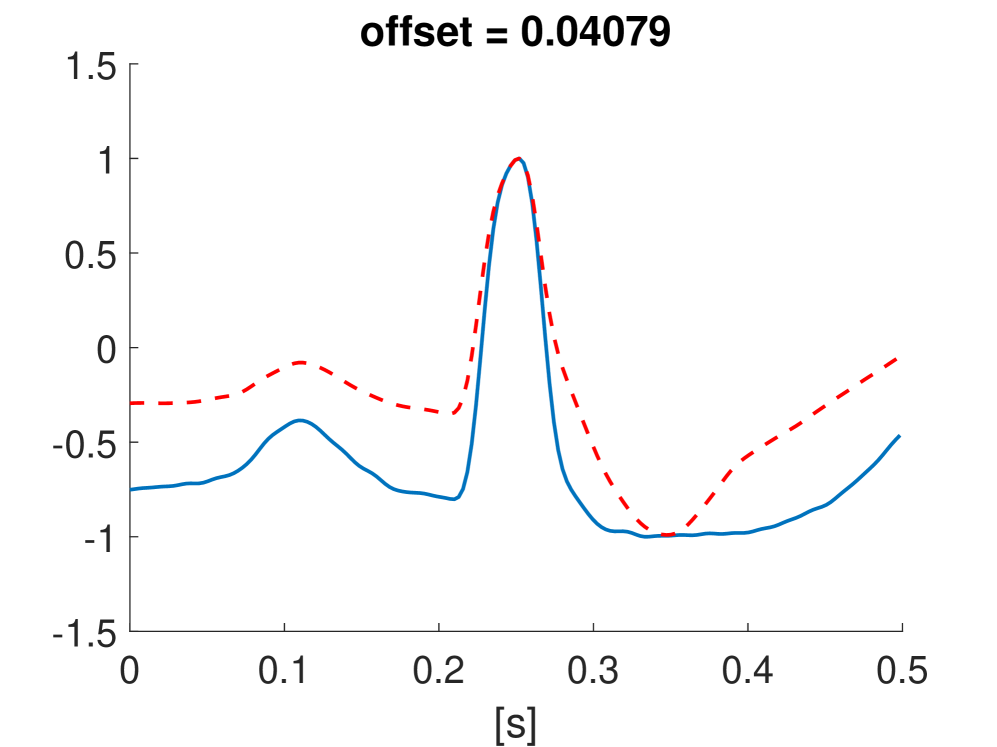

Fig. 10 shows the result in input space of moving along the first principal components in the latent feature space. As original base point we take a normal beat signal, i.e. corresponding to a hidden unit on the bottom right of Fig. 9(a). The smooth transition between the beat patterns allows for interpretation of the first principal components. This allows a clinical expert to understand on what basis the paced beats are separated by the principal components and if this basis has a physiological meaning. In order to investigate the separated region of the latent space at the top of Fig. 9(b) we start from a paced beat pattern and vary along the third principal component. This allows us to see which sort of heartbeat patterns are responsible for this specific distribution in the latent space.